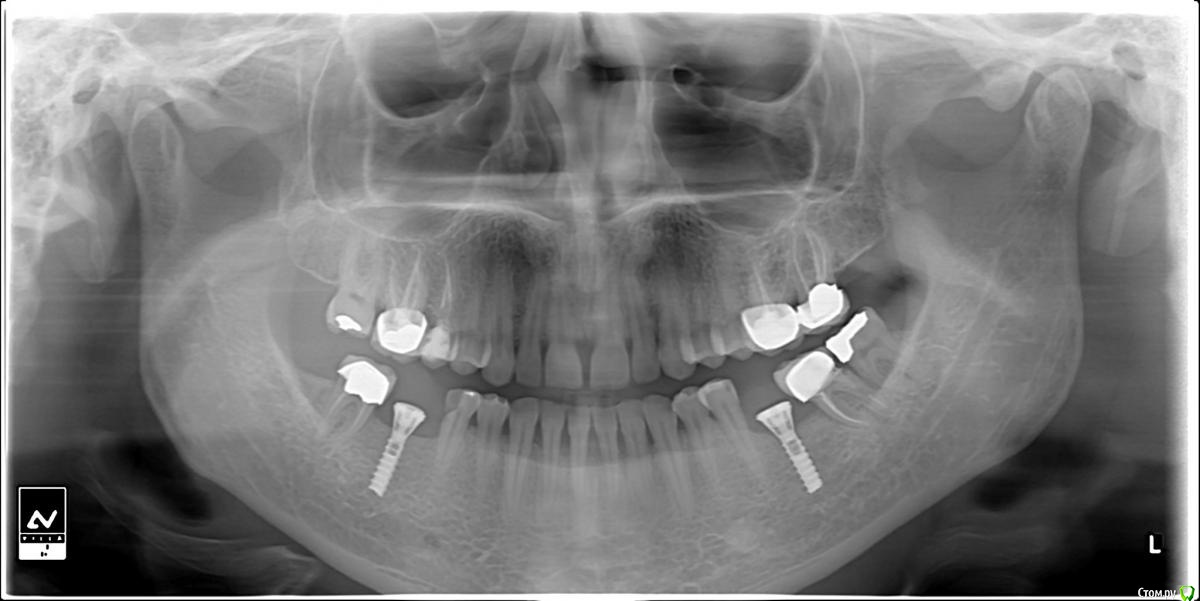

bilal Опубликовано 7 августа, 2016 Поделиться Опубликовано 7 августа, 2016 Помогите распознавать имплант. пациентка ставила 11 лет назад у другого доктора и уехала. Ссылка на комментарий

andr99 Опубликовано 9 августа, 2016 Поделиться Опубликовано 9 августа, 2016 Похоже на Straumann или на Blue Sky Bio, только не ясно,что с апексами.Нужной длины не было и решили подпилить?) Ссылка на комментарий

aka_sol Опубликовано 9 августа, 2016 Поделиться Опубликовано 9 августа, 2016 Похоже на Straumann или на Blue Sky Bio, только не ясно,что с апексами.Нужной длины не было и решили подпилить?)Точно не Straumann. 1 Ссылка на комментарий